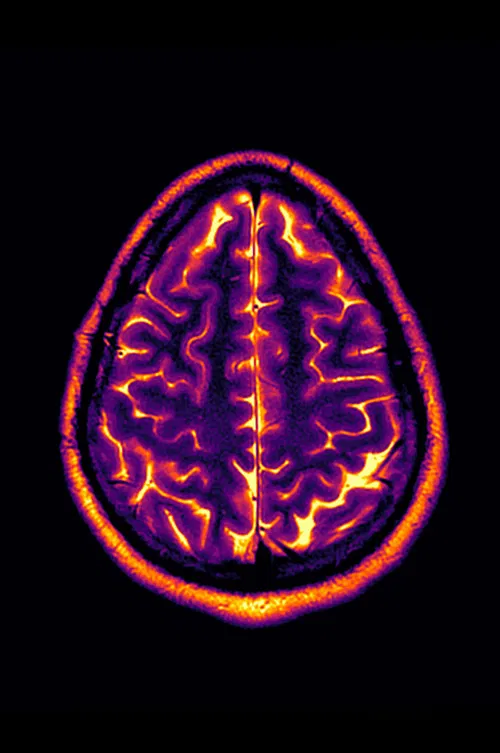

Living with a progressive disease like multiple sclerosis means annual tests and doctor’s visits, and with that comes the usual anxiety about whether this will be the year. Conclusion: Stable Disease is an experimental video made from the artist’s personal MRI image scans from 2018-2022